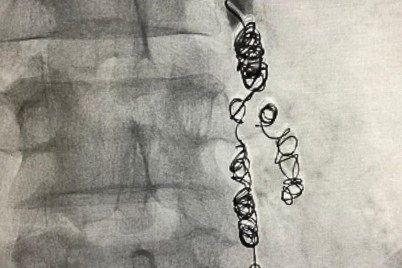

الرياض ـ منيفة الشمري نجح فريق طبي في مستشفى الأمير محمد بن عبدالعزيز أحد مكونات تجمع الرياض الصحي الثاني في...